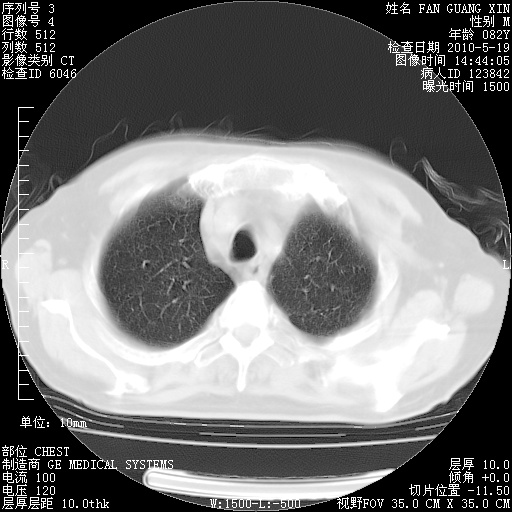

可改为口服强的松40-50mg/d治疗,若病情仍稳定,胸部阴影不再吸收可逐渐减量